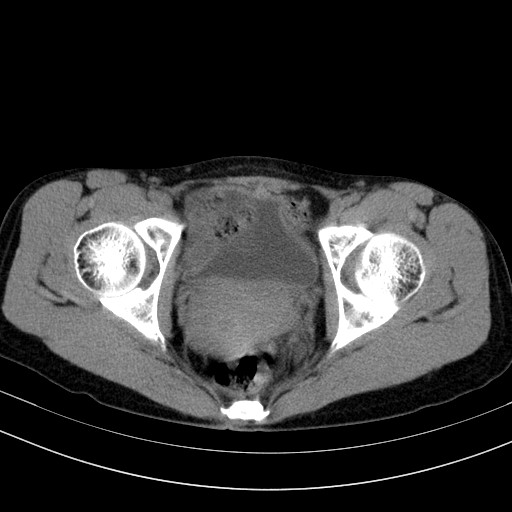

以下是引用随光逐影在2009-4-7 8:17:00的发言:[br]考虑宫颈占位性病变(宫颈癌?);建议行进一步检查。

以下是引用jiangjing在2009-4-7 16:46:00的发言:[br]宫颈增大,结构不清,右侧附件区可疑囊样占位,建议增强及mri 检查